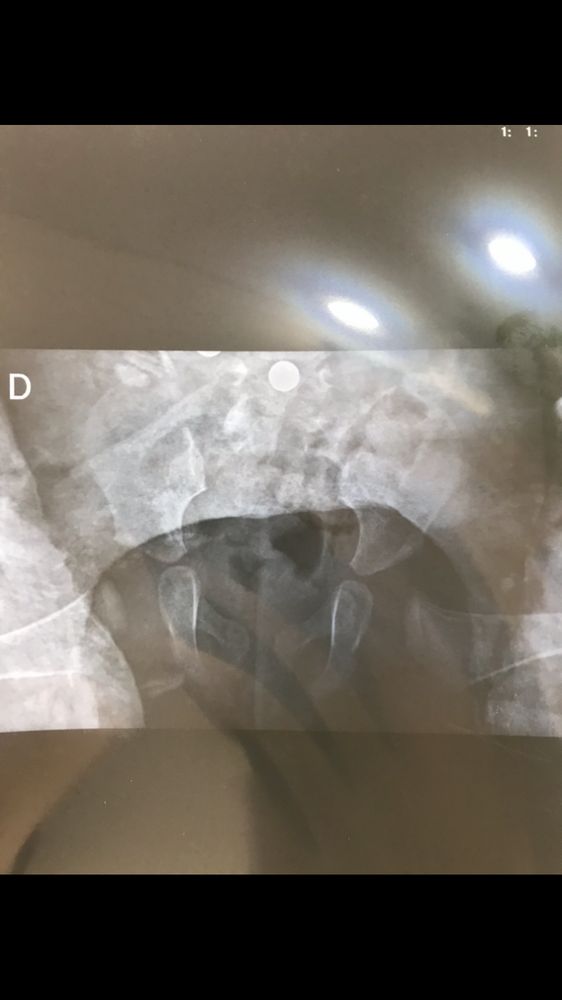

добрый вечер. у моего малыша дисплазия тбс с подвывихом. в марте вправили вывих и поставили гипс . хотелось бы узнать ваше мнение есть ли положительная динамика спустя два месяца в гипсе? нам немного изменили гипс и оставили его еще на два месяца.

Я удивлена, что вы в Питере, а лечитесь по московской школе - гипсом, а не шиной кошля. Мы в шине 24/7, на следующей неделе уже пол года как. По снимку сложно сказать. Желаю вам скорейшего выздоровления!